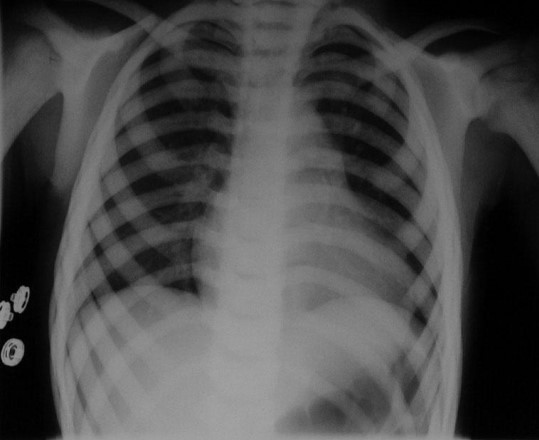

Common X-ray Findings: